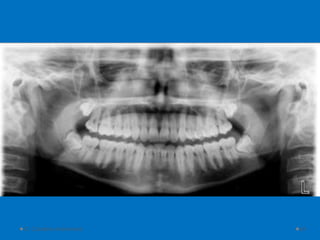

1.Activity

• Look at a printed OPG and mark major

features on the dental chart provided as you

doing a comparative AM profile.

• Look for :

• Cavities

• Fillings

• Bridegework

• Missing teeth

• Malocclusion

1.Activity • Look ata printed OPG and mark major features on the dental chart provided as you doing a comparative AM profile. • Look for : • Cavities • Fillings • Bridegework • Missing teeth • Malocclusion D. Caroline Mohamed 92